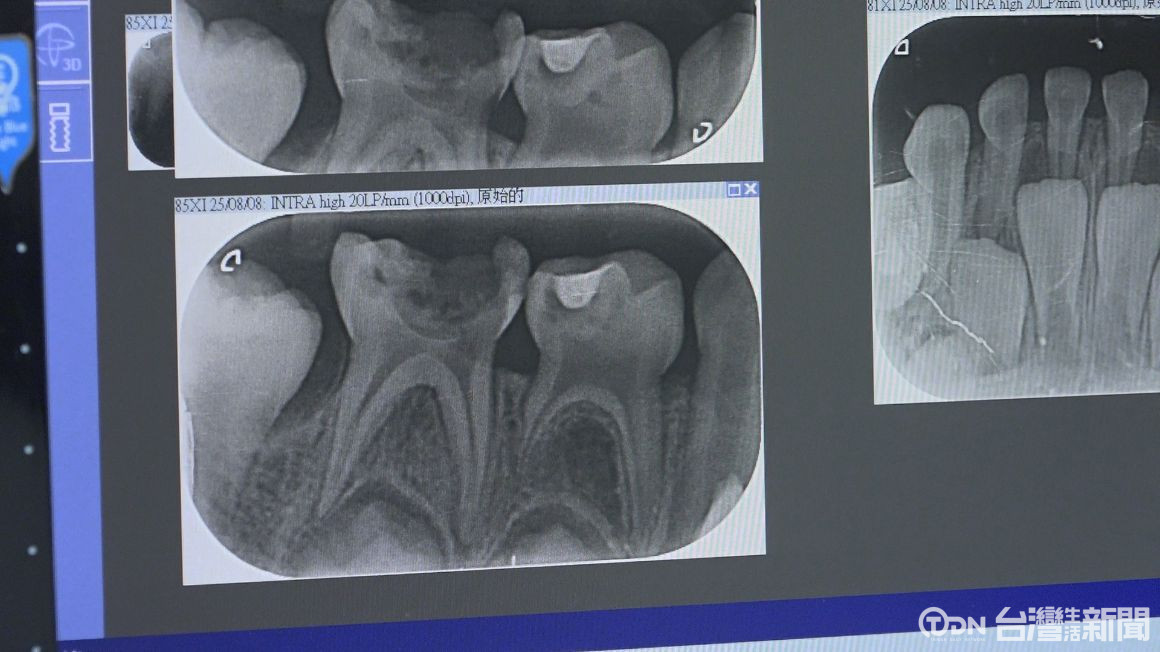

根據統計,台灣五歲兒童齲齒率高達四成六,遠超過世界衛生組織建議標準,因此為了強化預防,「口腔親善之家」,透過與婦產科、小兒科建立跨科綠色通道,讓嬰兒從0歲起就能接受口腔保健,而不是等到出現問題才就醫,這樣的預防性照護,不僅能降低孩子看牙恐懼,也能減少長期醫療支出。

▲根據統計,台灣五歲兒童齲齒率高達四成六,遠超過世界衛生組織建議標準/記者 陳柏翰攝